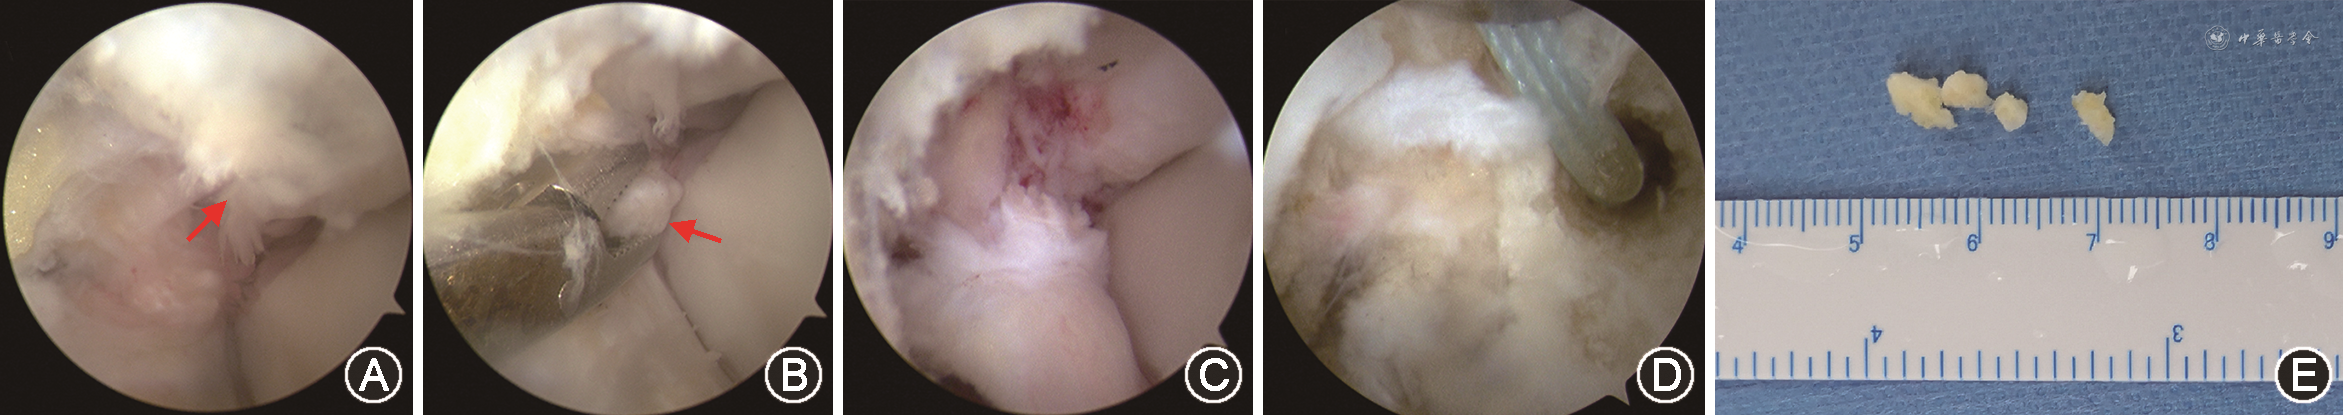

4.手术方法:(1)麻醉及体位:采用全身麻醉,患侧使用折叠托板,方便术中变更体位,患者采用平卧位,术中常规患侧大腿使用充气止血带加压止血。(2)术前准备:使用10 ml注射器穿刺关节腔并注入生理盐水充盈关节囊,拆除折叠托板,将患肢在末端悬吊重物牵引踝穴,增大踝穴间隙,更好地暴露外踝关节周围组织结构,方便进行踝关节内清理,清理完毕后,请巡回护士安装折叠托板,将患肢平放于手术台上进行镜下操作,进行外侧韧带加固。(3)踝关节外侧关节镜探查清理:所有手术操作均由同一术者完成,常规消毒铺巾后,止血带充气,于胫距关节水平胫前肌腱内侧建立踝关节镜前内侧入路,5 mm切口切开皮肤,保持踝关节背伸位同时,使用蚊式钳钝性分离皮下组织直至关节囊,置入2.7 mm关节镜;于踝关节水平第三腓骨肌外缘开口作为前外侧入路,蚊式钳钝性分离直至关节腔,此入路可作为器械操作通道,由于SFO常常包裹于距腓前韧带之中(图1A),术中需要使用动力刨刀(Arthrex CoolCut™ AR-8380DC)沿小骨周围清理,充分去除与小骨粘连组织,游离SFO,使用抓钳小心抓取SFO并经切口取出,小骨强度常常较低,加持时会导致其粉碎,无法完整取出,所以,镜下探查确认无残留是十分必要的;有时由于SFO较大,原手术切口需做适当延长;操作中尽量减少对SFO周围韧带的破坏(图1B),镜下探查确定无残余小骨后,改良Broström术[10]修复距腓前韧带,被动活动踝关节确定踝关节稳定性良好;所有患者均在不同程度上进行了踝关节间隙内增生滑膜组织的清理,有2例患者伴有距骨软骨损伤术中同时进行了清理及微骨折治疗。

术前比较双侧踝关节应力位X线片,可见踝关节稳定性可(图1A、B、C、D),双下肢力线良好(图1E),踝关节CT及MRI检查显示SFO的存在,并与周围韧带组织相连(图1F~I),术前测量SFO最长径为(4.1±1.4)mm,其中9例(60.0%)<5 mm,6例(40%)为5~10 mm;所有病例SFO均完全取出(图2),术后复查踝关节CT可见SFO完全消失(图1I)。患者术中见SFO均包裹或附着于距腓前韧带,周围伴有滑膜组织和瘢痕组织增生(图3)。